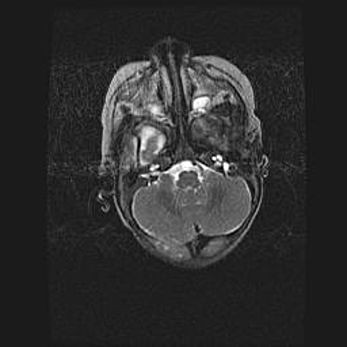

Лейкомаляция с кистозно-глиозной дегенерацией головного мозга.

Возраст: 2 месяца 25 дней

Вес: 6400 г

Окружность головы: 40 см

Срок гестации: 41 неделя

Лейкомаляцию относят к ишемически-гипоксическим повреждениям головного мозга, диагностируемым у новорожденных. При лейкомаляции в головном мозге обнаруживают очаги некроза, возникшие после тяжелой гипоксии и нарушения кровотока. В процессе морфогенеза очаги проходят три стадии: 1) развития некроза, 2) резорбции и 3) формирования глиозного рубца или кисты. Перивентрикулярная лейкомаляция (ПЛ) встречается примерно в 12% случаев среди новорожденных, обычно – у недоношенных детей, причем, частота ее зависит от массы, с которой младенец появился на свет. Наибольшее число малышей страдает лейкомаляцией, если масса при рождении 1500-2500 г.